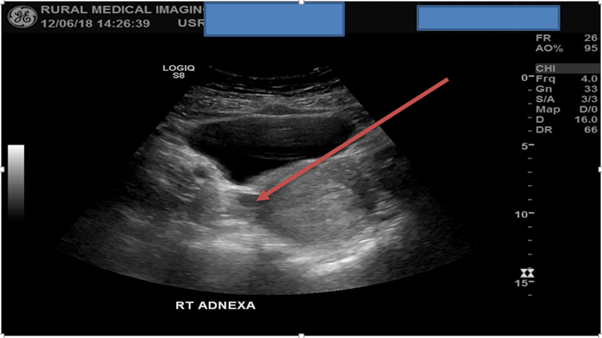

A scan of the left adnexa in the transverse plane from inferior to superior concluded that no pathology was detected but failed to observe the left ovary. A second sweep now of the right adnexa observed a well-defined anechoic lesion near the interstitial fallopian tube region. A possible GS was suspected, no obvious yolk sac or foetal pole was detected within the lesion. Literature states that the risk of an EP can exceed 90% when there is no detectible IUP and there is a corresponding adnexal lesion present. [1]

Figure 3: TAS detects a well-defined anechoic lesion observed near the right interstitial fallopian tube region, highly suspected of being an EP.